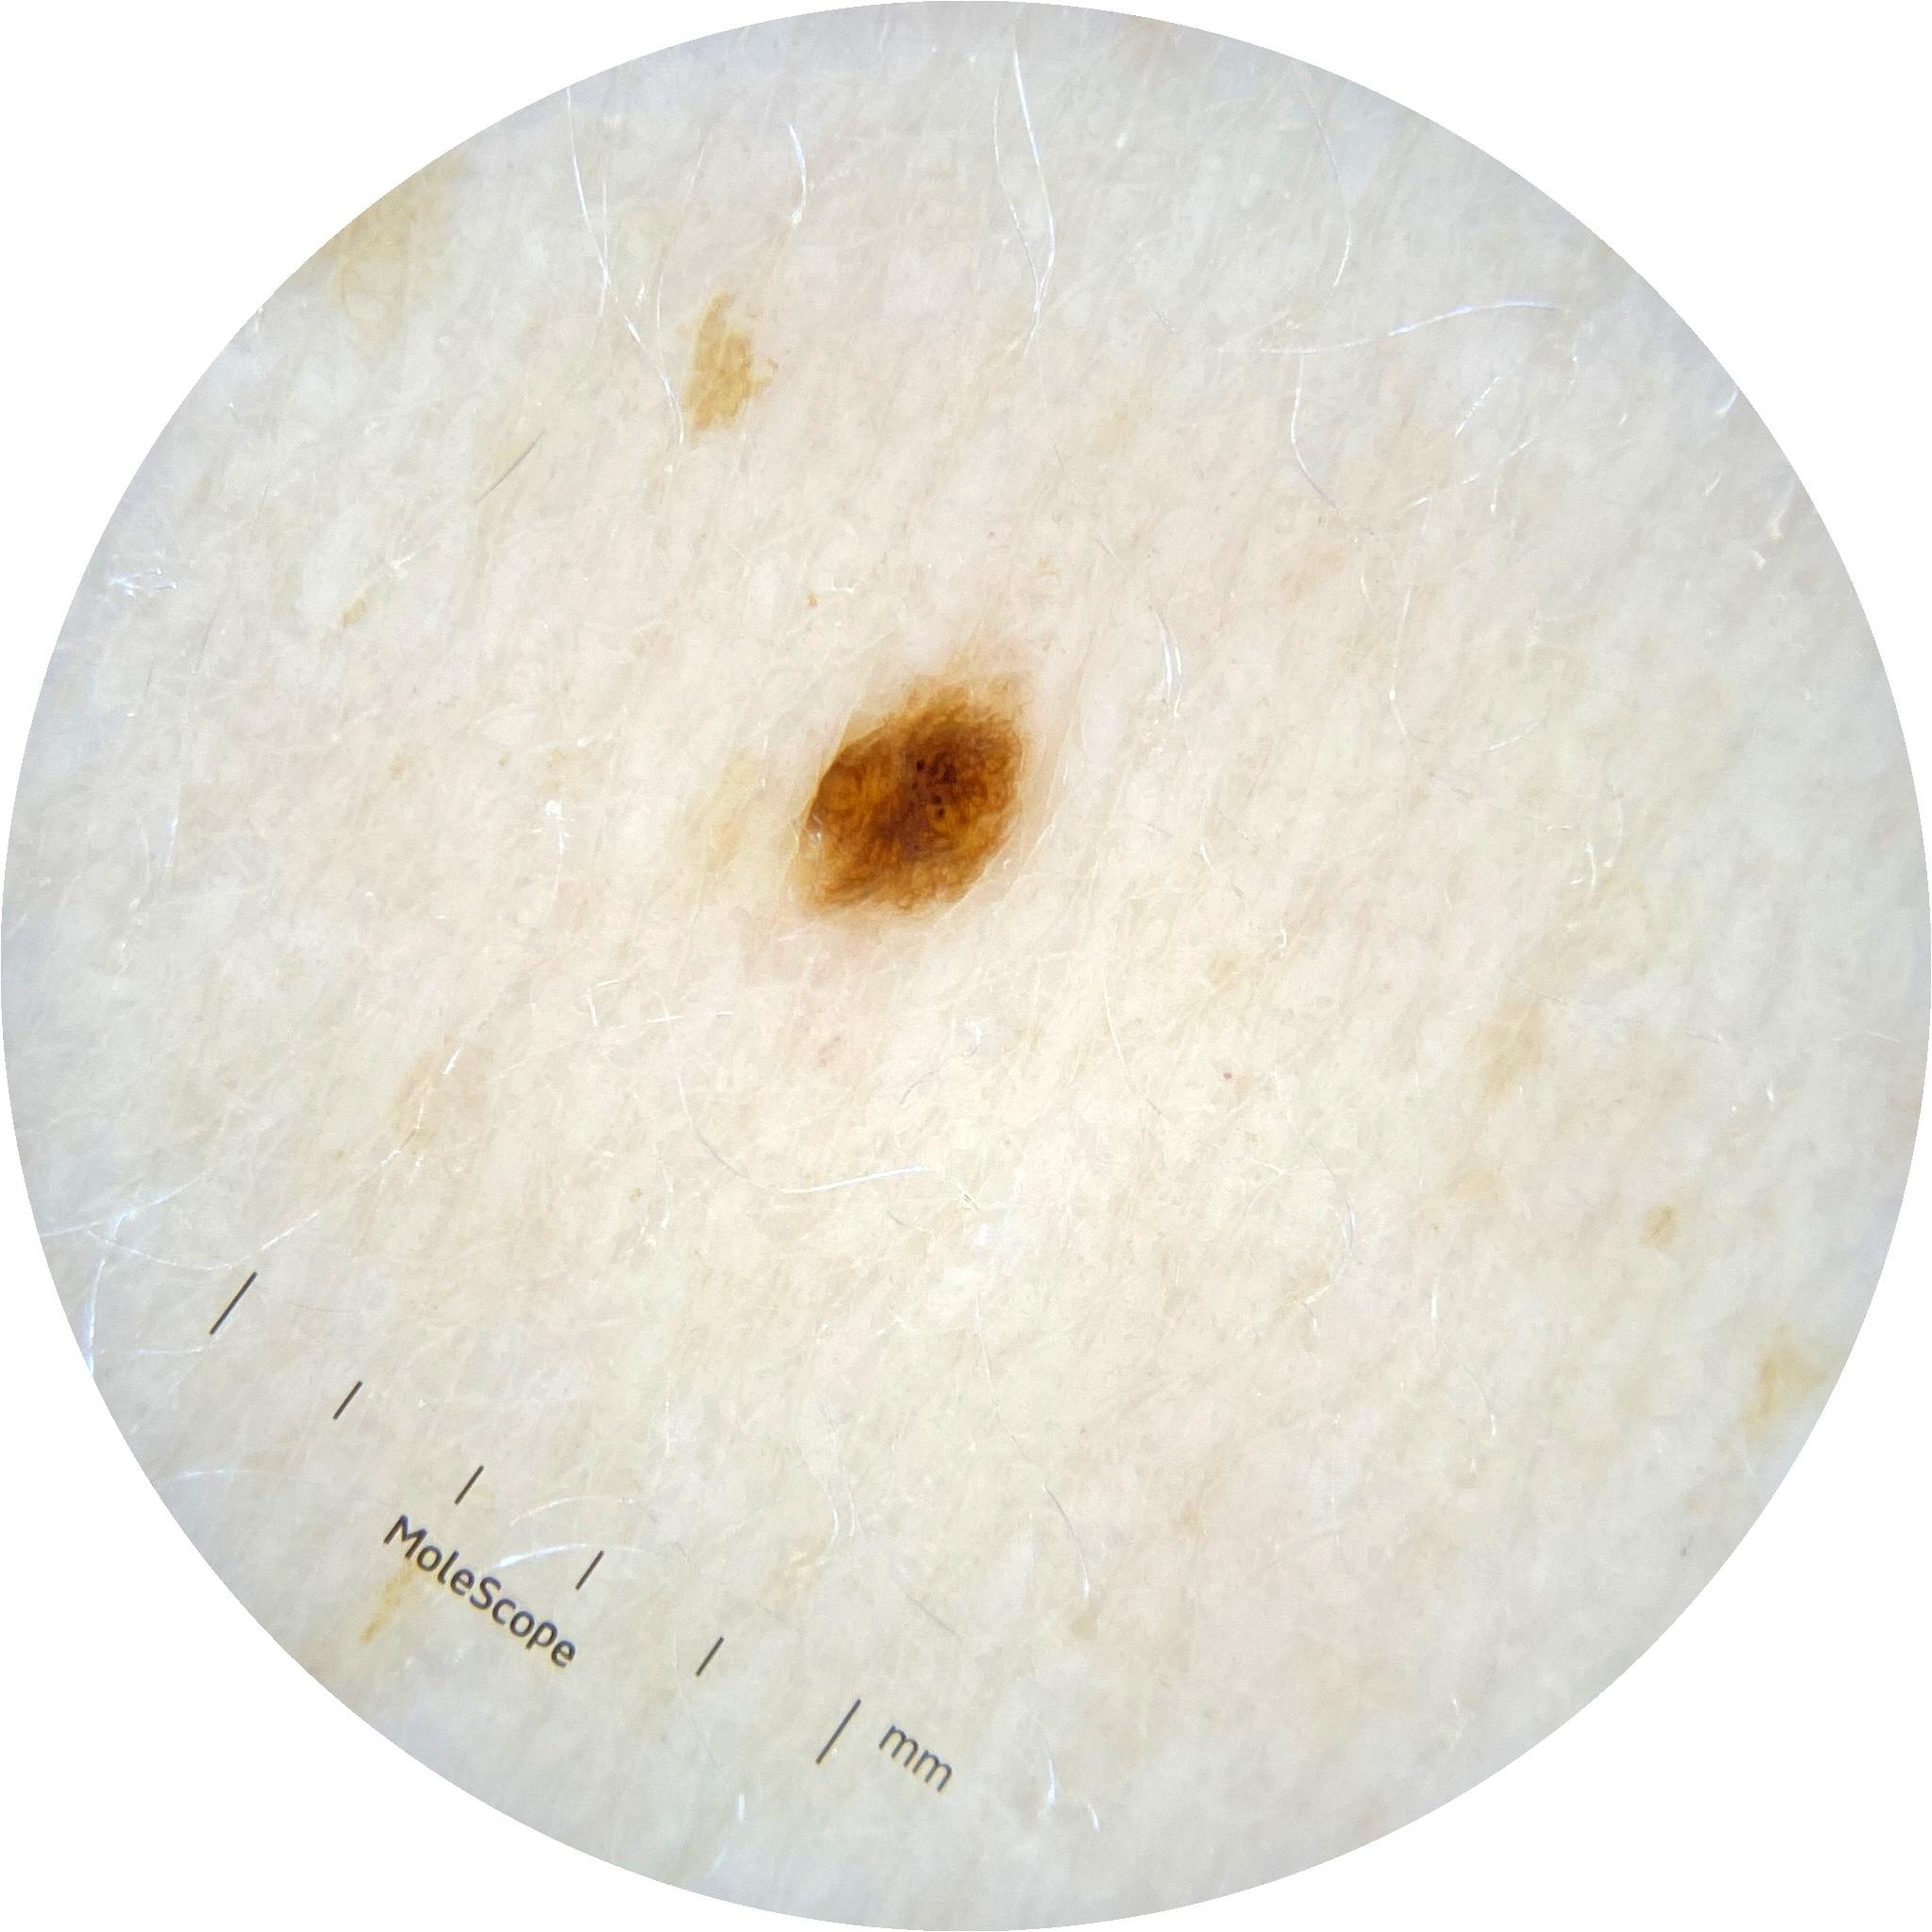

ISIC_2261268

2061 x 2061

acquisition_day 307

age_approx 50

anatom_site_1 Trunk

anatom_site_2 Posterior trunk

anatom_site_general posterior torso

diagnosis_1 Benign

diagnosis_confirm_type single image expert consensus

image_type dermoscopic

personal_hx_mm True